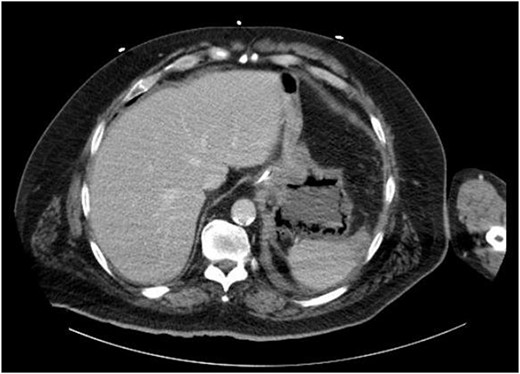

On evaluation, the patient was afebrile, tachycardic to 107 bpm, with BP 112/63 and RR 21. On exam, he appeared diaphoretic and had left upper quadrant tenderness without rebound or guarding. He was otherwise alert and oriented. His white blood cell count was 22.5 with 13.1 bands, and lactate of 6.2, which improved with IV fluid resuscitation. Computed tomography (CT) abdomen and pelvis demonstrated pneumatosis of the proximal gastric wall (Fig. 1), and mild portal venous gas. He was started on antibiotics and antifungals; a nasogastric tube was placed for decompression, and he was started on parenteral nutrition; however, he failed to improve clinically, with continued abdominal pain and tenderness, and persistent tachycardia. A repeat CT after 5 days of treatment redemonstrated gastric wall pneumatosis (Fig. 2), though with resolution of the portal venous gas.